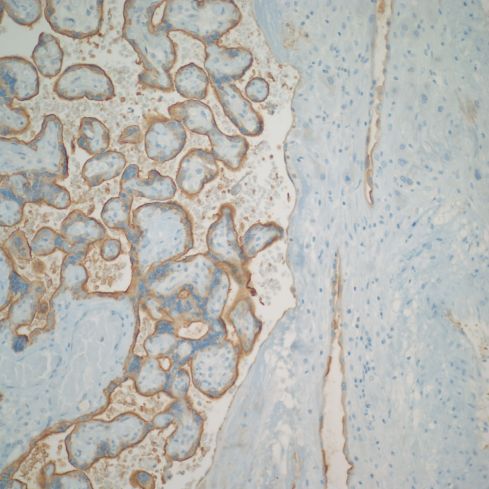

The lining of base of the placenta on the intervillous surface appears to have an endothelial phenotype, as do vessels that are likely veins. The arteries maintain a trophoblast phenotype, but more systematic studies may show less of a dichotomy (Figs 30,31).

Fig 30: This normal mature placenta demonstrates villi with brown staining from an antibody to placental alkaline phosphatase (PLAP) present on the surface of the villous trophoblast. The basal decidua runs along the right of the image. The spiral arteries are also lined by brown stained cells indicating that the lining cells are trophoblastic. (PLAP, 20x)